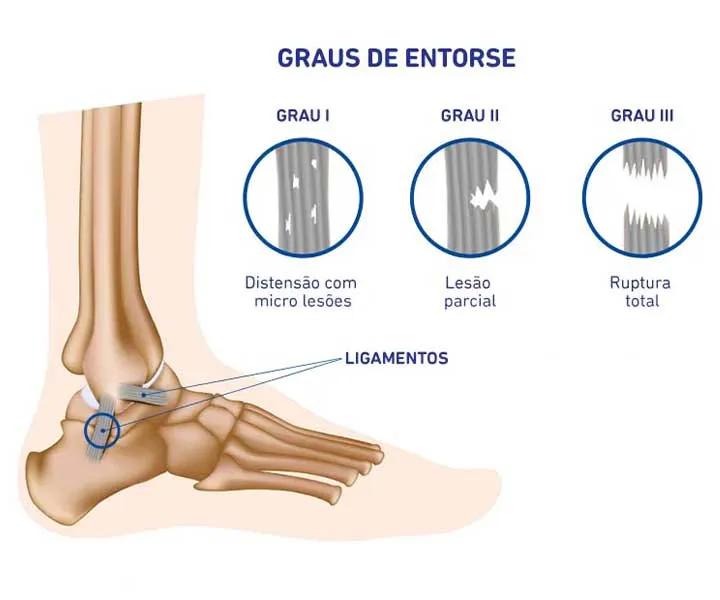

Existem diferentes graus de entorse: